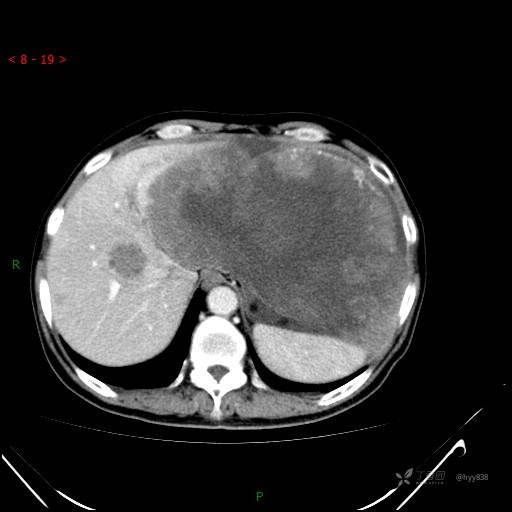

腹部CT平扫

增强动脉期

增强静脉期